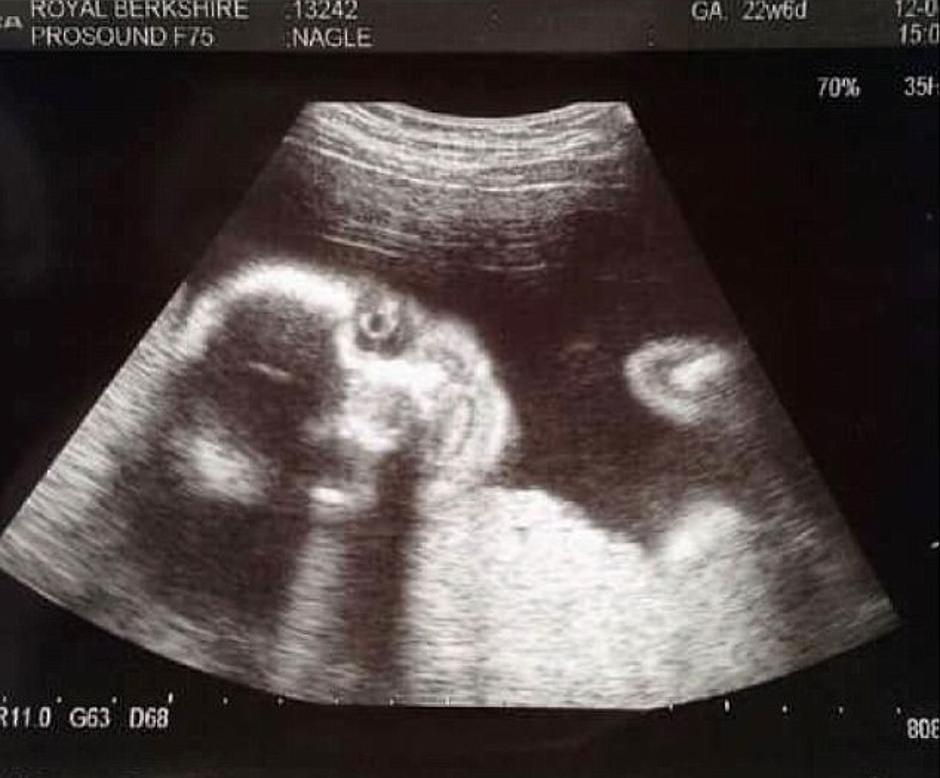

No, prva fotografija sina koju je dobila kada je bila trudna 20 tjedana, nije oduševila 25-godišnju Sophie Nagle.

Dječak sada ima dvije godine, a njegova majka odlučila je javno podijeliti fotografiju s ultrazvuka koja nije šokirala samo nju već i tehničarku koja ju je snimala.

- Odlučila sam se na 3D ultrazvuk, no kada sam vidjela prvu fotografiju malo je reći da sam se šokirala. Ostale smo zaprepaštene i ja i tehničarka koja je radila ultrazvuk - ispričala je ova majka.

Na snimci se dječak smiješi, no to nije osmjeh kakav biste voljeli vidjeti jer više podsjeća na Jokera iz Batmana nego nevino novorođenče.

Sreća, maleni Ruben danas ima puno nježniji osmjeh koji može rastopiti srca mnogih.